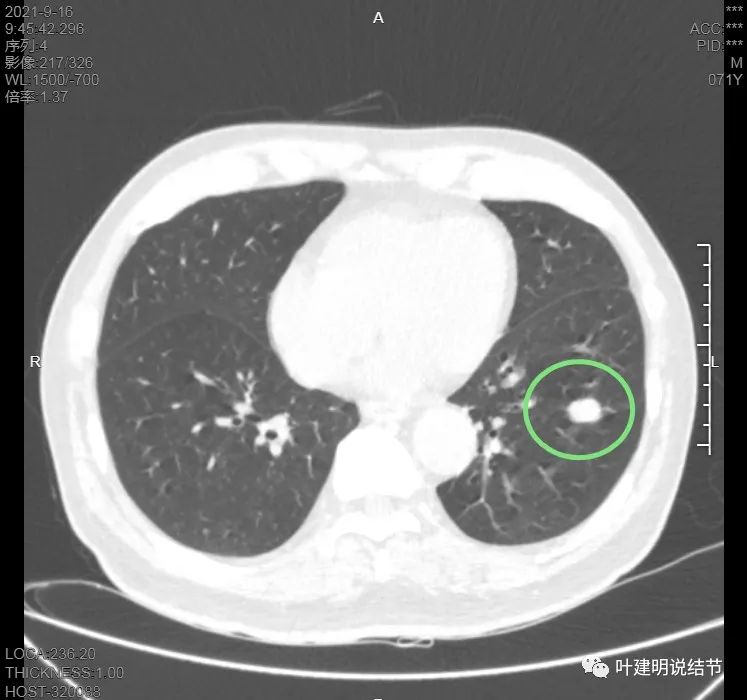

上图是病灶下缘的样子

这样的病灶应该是良性可能性大的多,纵隔窗上又是如何的呢?